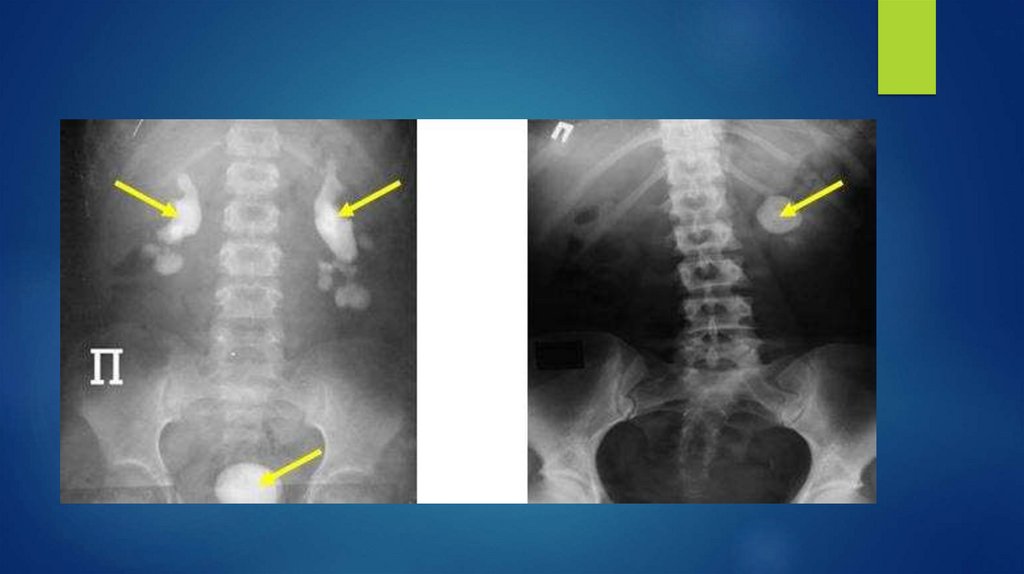

Ретроградная уретеропиелография

Антеградная пиелоуретерография

Цистография

44. Экскреторная урография

На 7, 15, 25, 40 минуте

45. Нефроптоз

a-лежа, b-стоя

46. Тазовая эктопия почки

47. Гидронефроз